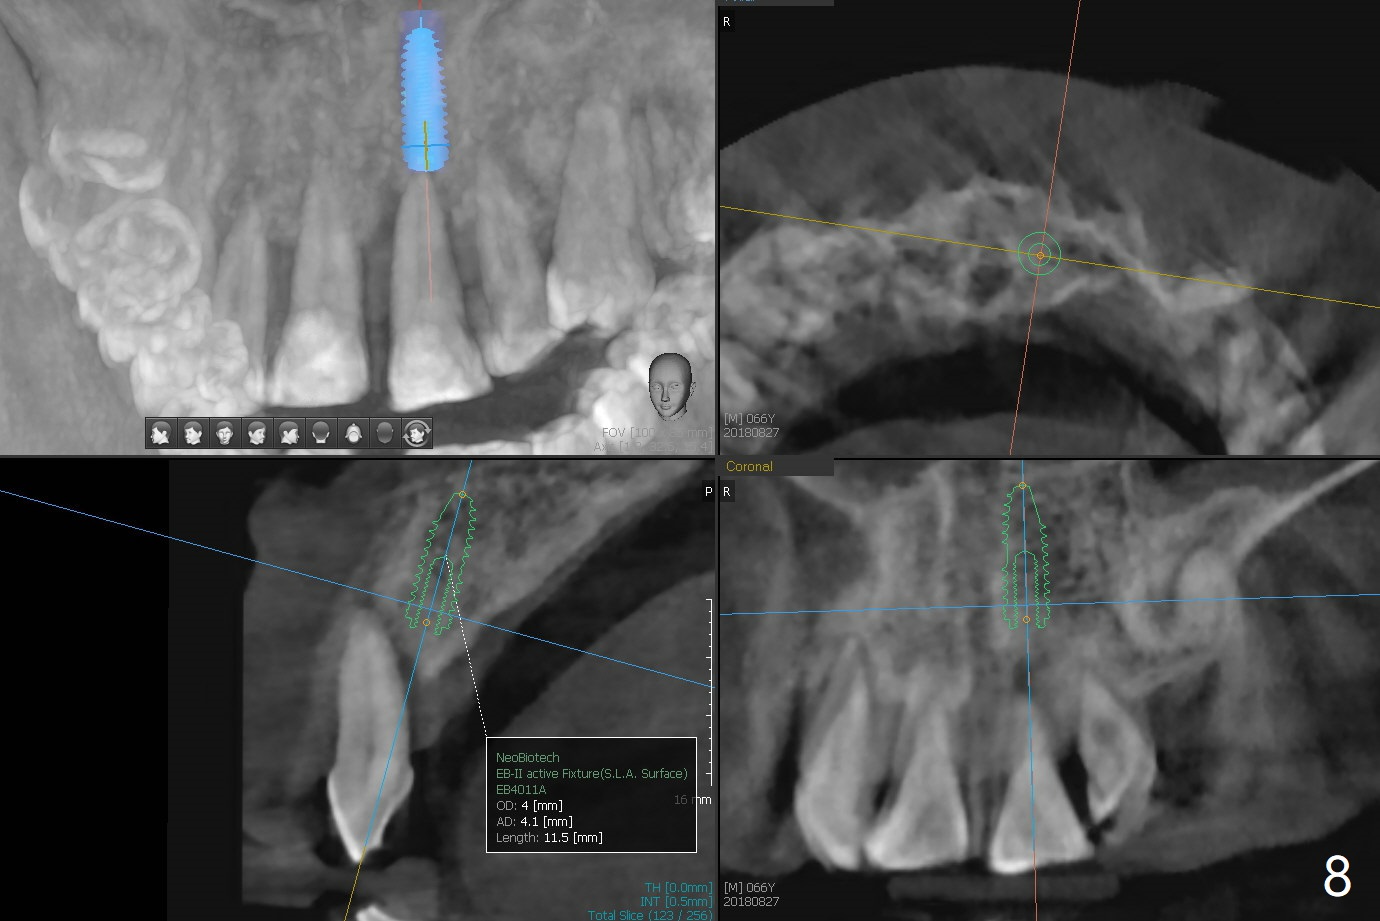

A 67-year-old man requests extraction of the loose tooth #9 (Fig.1). After extraction, the labial plate is found to be missing. With incision, allograft is kept in place with a 12x24 mm anterior narrow Cytoplast and 4-0 Chromic gut suture (Fig.2). Periodontal dressing dislodges in 2 days. The wound dehisces transversely 5 days postop (Fig.3 arrows), whereas the wound was open buccopalatal when the sutures were placed. Probably due to extensive dissection, the erythematous mucosa is large (Fig.4), although asymptomatic. When X-ray shows V-shaped bony defect (Fig.1 (PA), 5 (Pan), 6 (CT)), do not dissect the overlying thin buccal gingiva, which is most likely to dehisce. In fact immediate implant with guide appears to be more conservative, since there is no pressure against the buccal gingiva (Fig.7,8). To be more ideally, the implant could be placed more coronally, longer (13 mm instead of 11.5, Fig.9,10) and narrower (3.5 mm instead of 4.0 mm, Fig.11 (red circles: bone graft)).